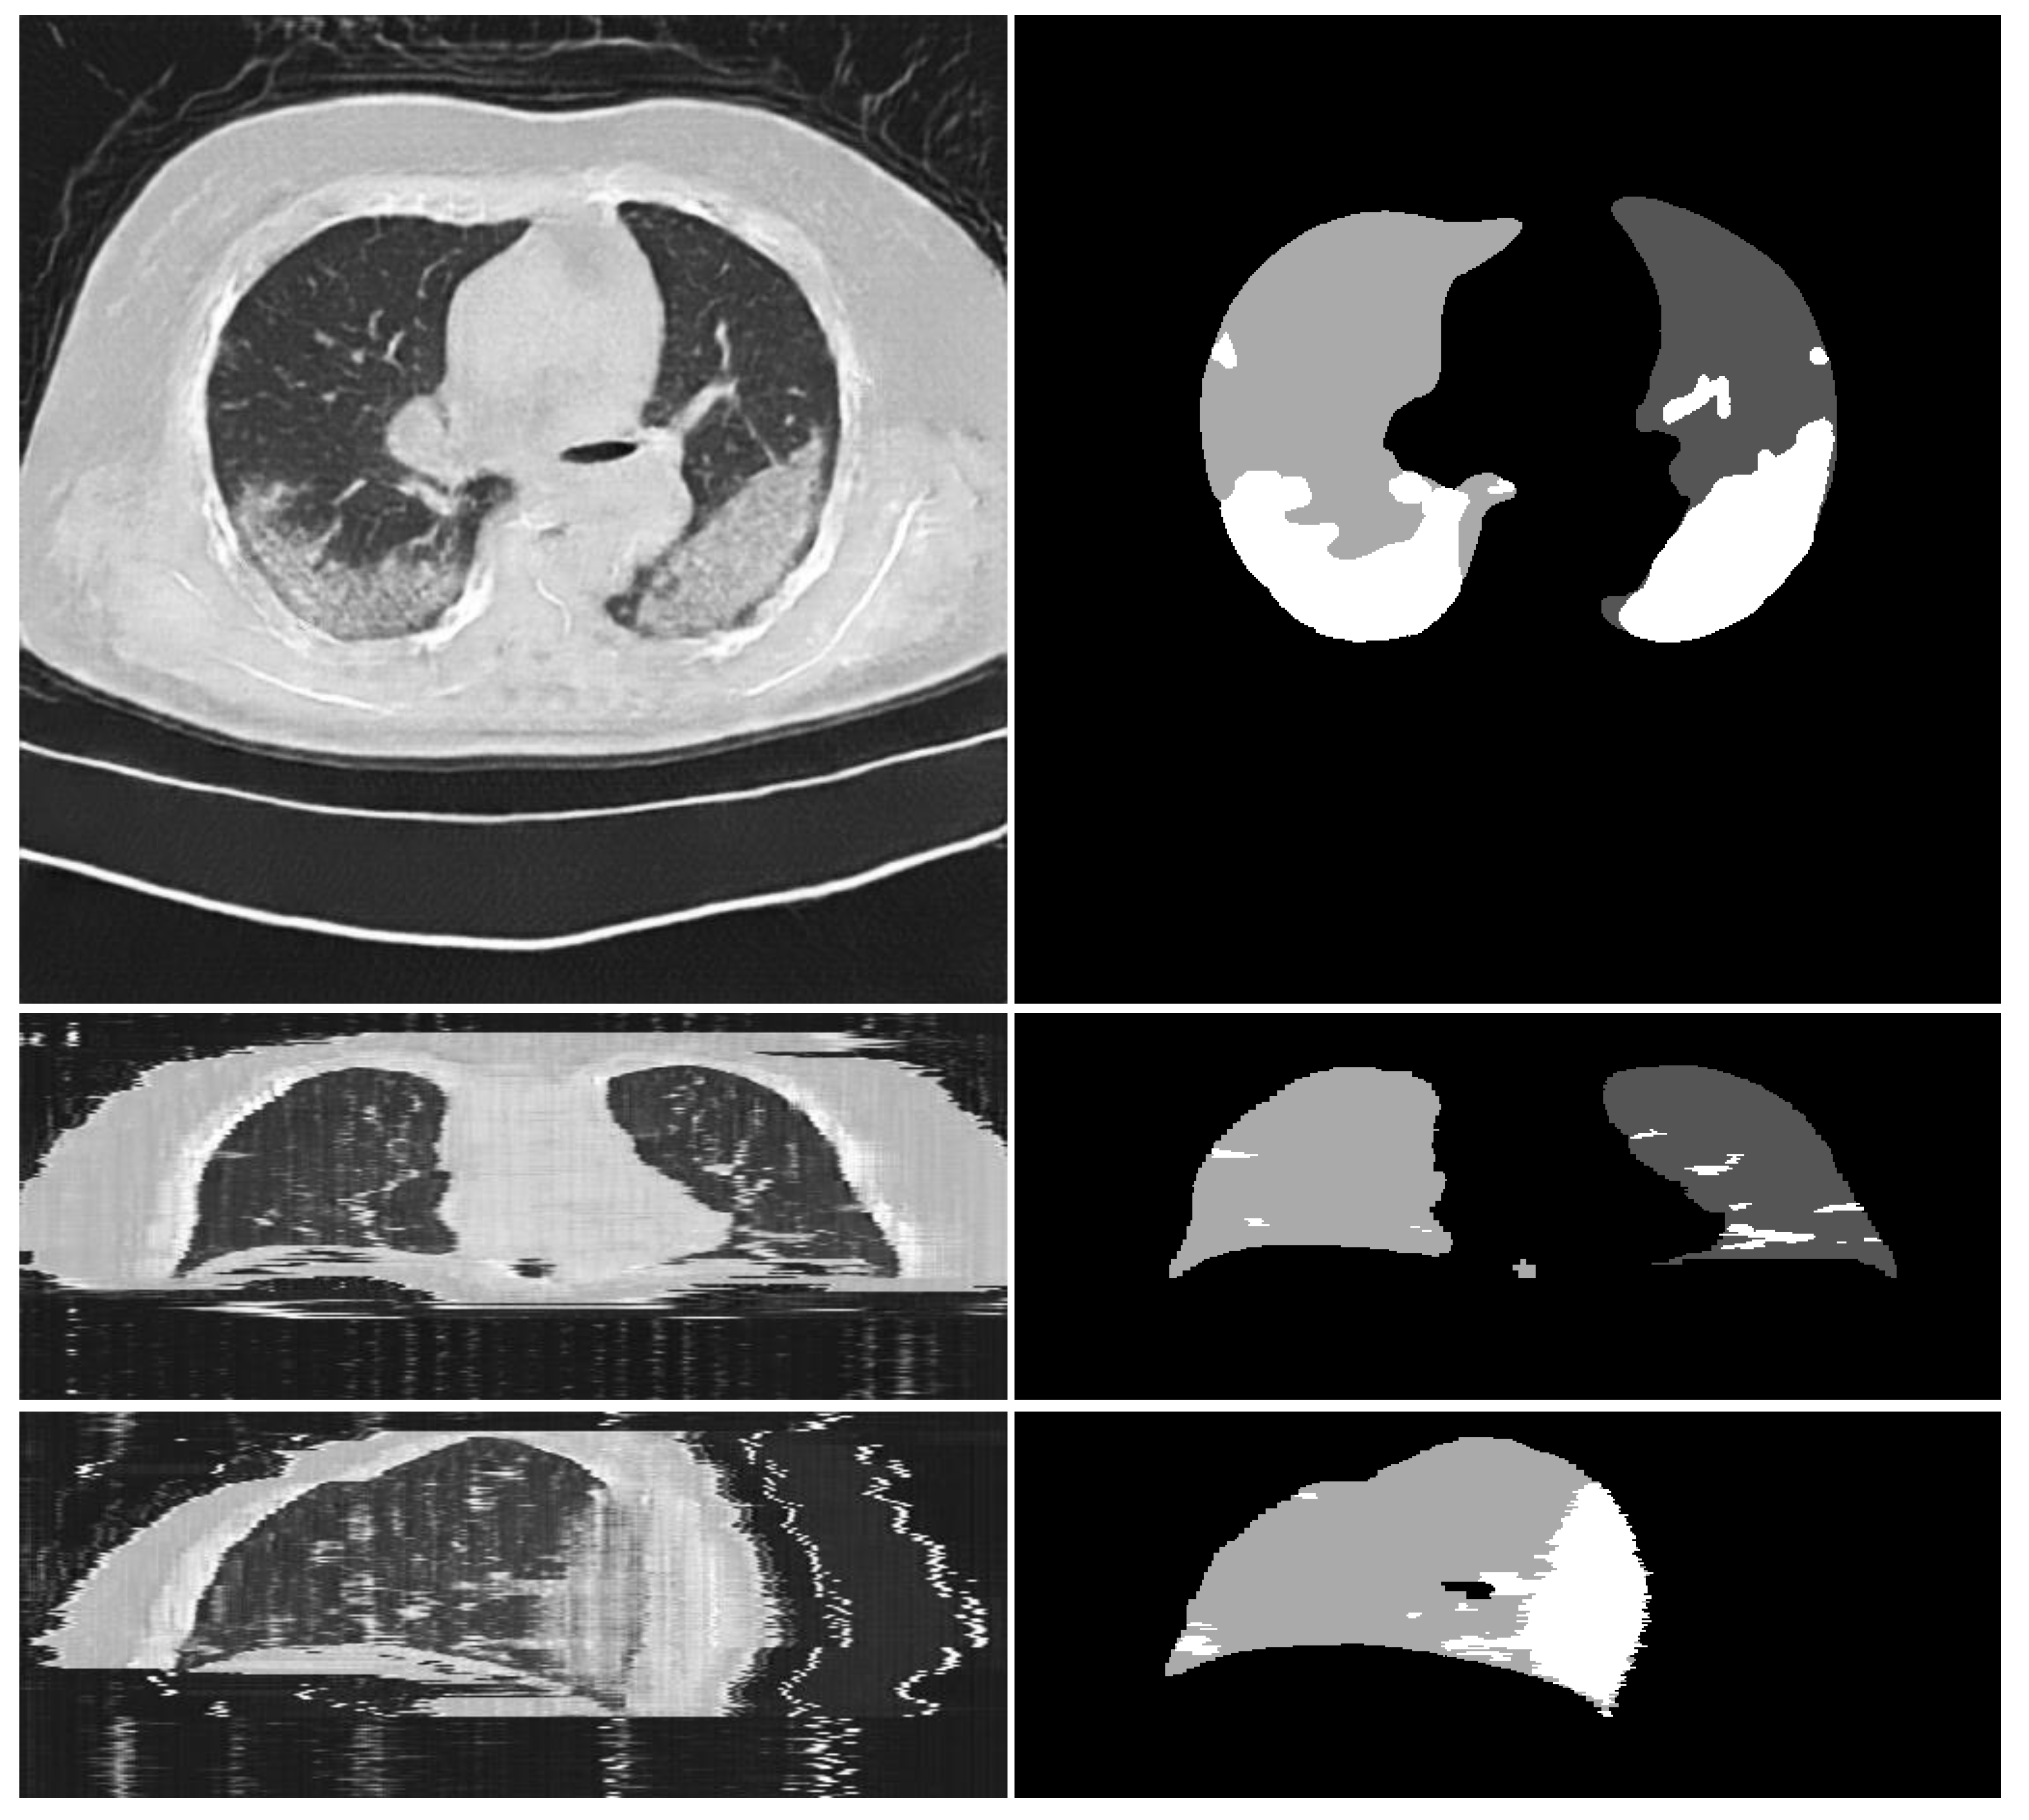

3.1. Experiments on Synthesizing Radiological Images

3.1.2. Ablation Experiments

- Qualitative comparison